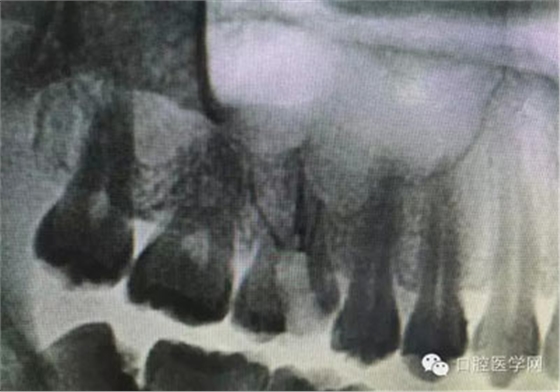

根管治療,我們?cè)诖髮W(xué)的時(shí)候就學(xué)習(xí)的東西,標(biāo)準(zhǔn)就在那里放著,可是很多時(shí)候我們熟視無(wú)睹,放任我們的想象去做。我們多些重視,多些心思,會(huì)好很多,認(rèn)真對(duì)待每顆牙齒。